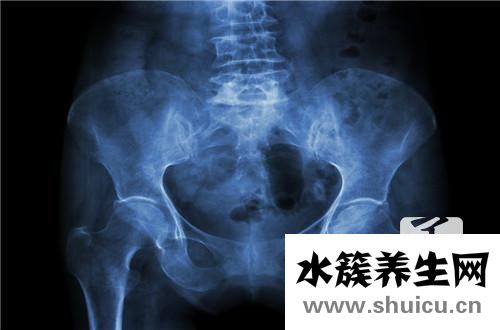

盆腔炎是女性最常見的癥狀之一。如果盆腔炎存在,女性的整個生殖系統(tǒng)將受到極大的影響。為了避免這種影響進一步擴大,有必要采取合理的方法及時治療盆腔炎。藥物治療是治療盆腔炎的常用方法。現在,讓我們介紹一下盆腔炎的藥物治療。